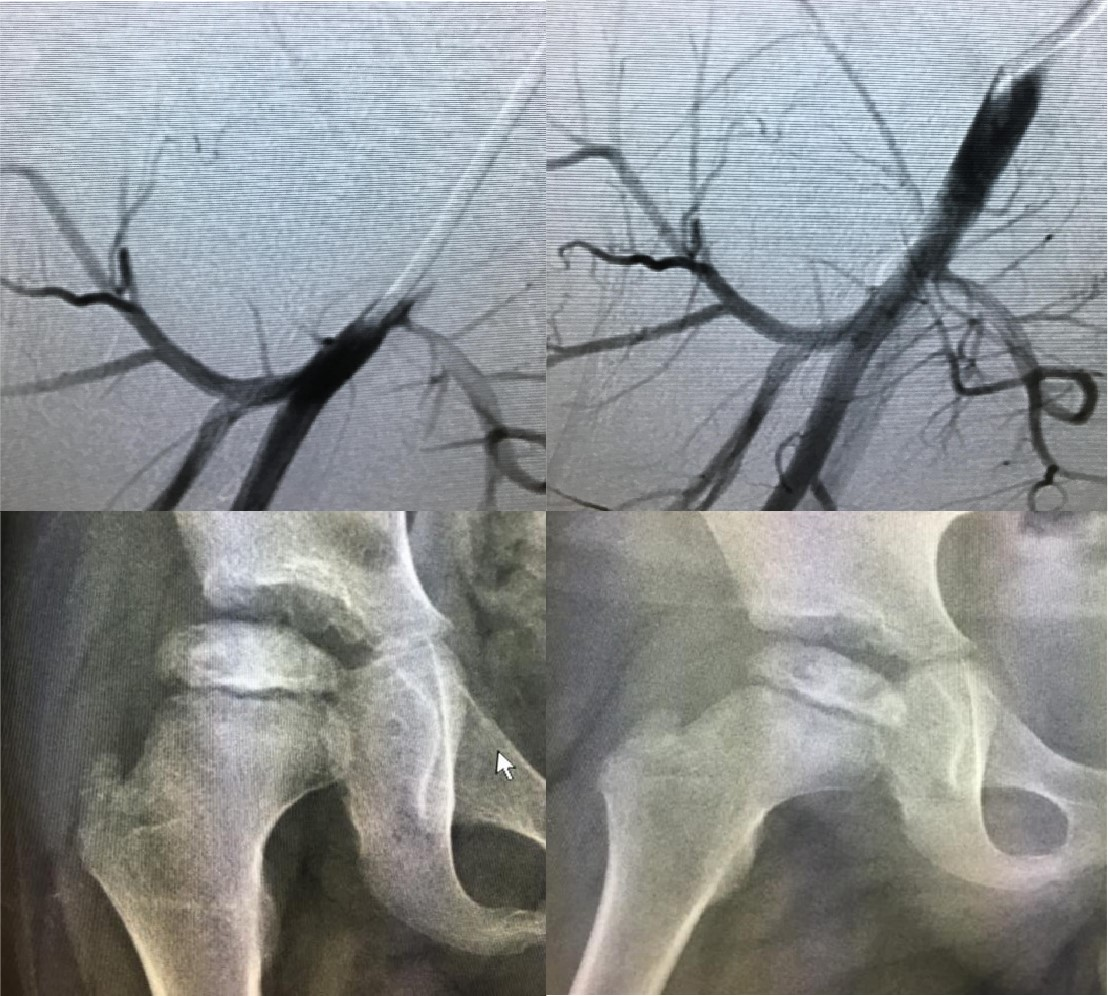

儿童股骨头无菌性坏死

儿童股骨头无菌性坏死,又称Perthes病,系一种发病原因不明确的综合征。表现为股骨近段和股骨头骨骺的缺血性改变。密度增高的股骨头随后吸收而由新生骨代替。在这一过程中股骨头的力学特性发生改变,显示扁平和扩大,最后再逐渐塑形。Perthes病的特点:1、缺血以及不同程度的骨坏死,致残率极高;2、原因不明,缺血是其直接因素;3、外科一般通过开窗减压治疗,创伤大,可重复性差;4、可以通过超选择动脉内灌注溶栓、扩血管药物治疗。疗效快,创伤小,可重复性强;5、部分患儿可以自愈、但会出现自限性畸形。

12、经导管动脉灌注治疗儿童股骨头无菌性坏死;

13、经导管动脉化疗栓塞治疗肝/肾母细胞瘤;